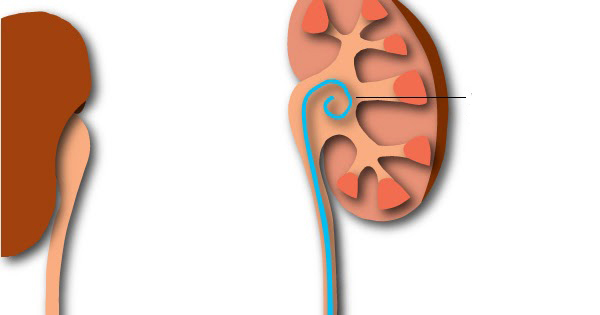

Catéter Ureteral Doble J

¿Qué es este catéter? El catéter ureteral doble J es un catéter de fino calibre diseñado para ser colocado dentro de los conductos anatómicos desde la vejiga hasta el riñón cuando existe alguna obstrucción al pasaje de la orina y así asegurar el paso de orina desde el riñón hasta la vejiga. El catéter simple … Continuar leyendo Catéter Ureteral Doble J